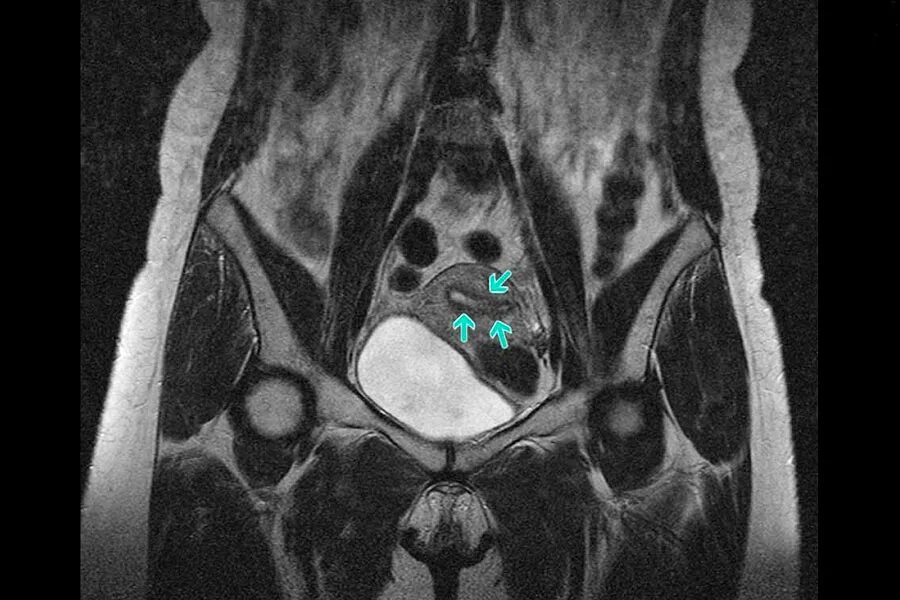

Метастазы в матке